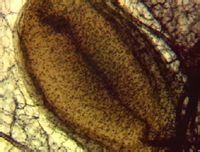

環層小體體積大,圓或卵圓形,分布於皮下組織、腸系膜、關節囊、某些內臟等處,感受壓覺和振動覺。圖示皮下組織中的環層小體橫切面,外為數十層同心圓排列的扁平細胞構成的被囊(C),中央有一條均質圓柱體,稱內棍(箭頭)。皮膚,HE染色

(2)環層小體(lamellar corpuscle):又稱潘申尼小體(Pacinian corpuscle),此種小體分布廣泛,多見於真皮深層、皮下組織、腸系膜和胰腺的結締組織中。小體多呈圓形或橢圓形,大小不一其直徑約為0.5~3mm。小體的被囊是由扁平的結締組織細胞和纖維形成的同心圓板層,板層間充滿膠樣物質。小體的中軸為一均質性的圓柱,稱內棍(inner bulb)神經纖維失去髓鞘後進入內棍,主要是感受壓力、振動和張力覺等。

環層小體透射電鏡下,小體外周是幾十層結締組織扁平細胞疏鬆排列所形成的同心板層的被囊,板層之間充以液體,被囊表面還有一層富於彈力纖維的鞘膜包裹,中央為失去髓鞘的軸突,軸突內含有線粒體和位於軸突下直徑約50nm的緻密核芯小泡,中央則有細絲和微管,被囊同心板層近中心部有大量緊密連線、環抱軸突終末的片狀胞質板,上有縫隙連線,在軸突終末的軸膜上有含細絲束的軸突棘,突入兩側扁平胞突的裂隙內。